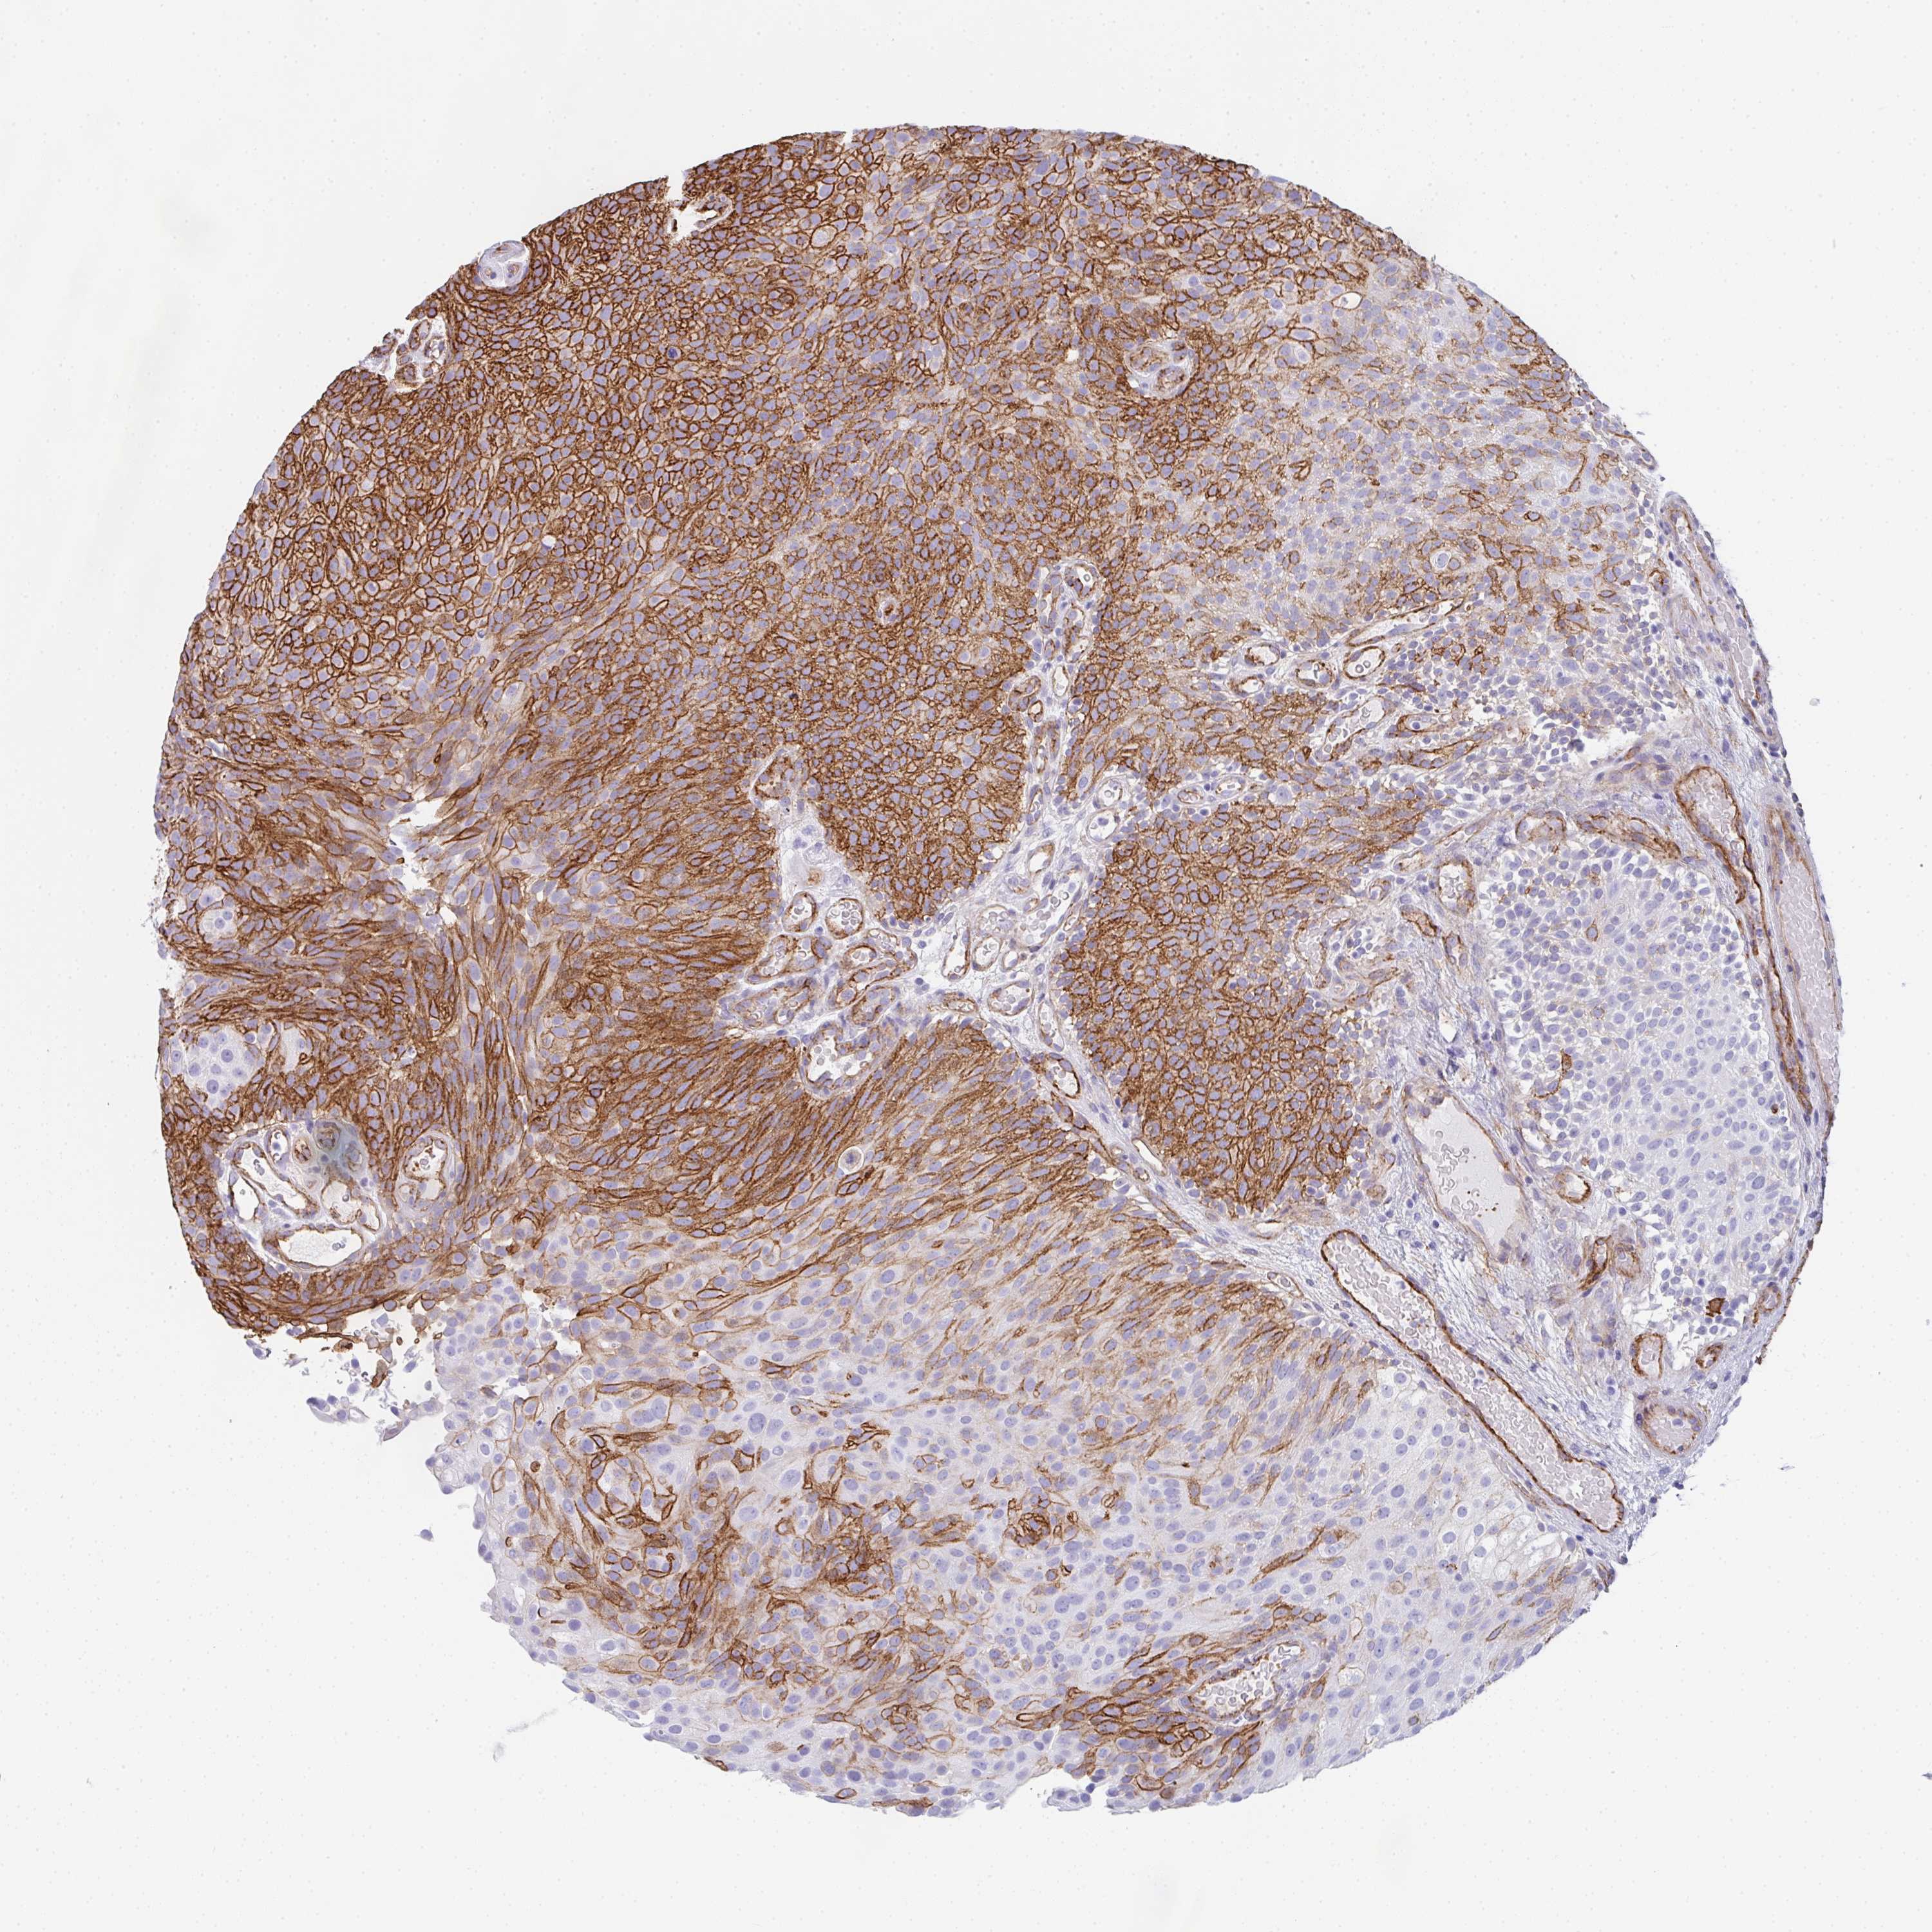

UROTHELIAL CANCER - Protein expressioni

A mouse-over function shows sample information and annotation data. Click on an image to view it in a full screen mode. Samples can be filtered based on level of antibody staining by selecting one or several of the following categories: high, medium, low and not detected. The assay and annotation is described here.

Note that samples used for immunohistochemistry by the Human Protein Atlas do not correspond to samples in the TCGA dataset.

Antibody stainingi

Antibody staining in the annotated cell types in the current human tissue is reported as not detected, low, medium, or high, based on conventional immunohistochemistry profiling in selected tissues. This score is based on the combination of the staining intensity and fraction of stained cells.

Each image is clickable and will lead to virtual microscopy that enables deeper exploration of all samples and also displays staining intensity scores, fraction scores and subcellular localization as well as patient and tissue information for each sample.

Antibody HPA051452

Antibody HPA056940

Urothelial carcinoma, High grade

Urothelial carcinoma, Low grade